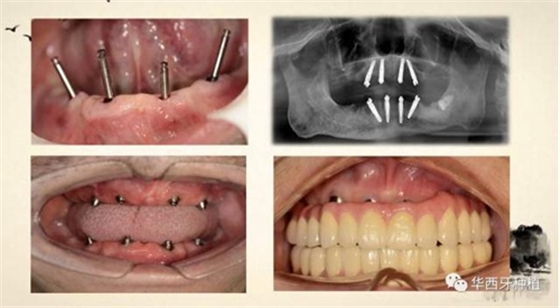

接下來吳教授分別針對幾種具有不同特征的病例,進(jìn)行分析、設(shè)計(jì)與病例回顧。對于不同骨量缺失的全口牙缺失患者,可選的種植修復(fù)方式有較為傳統(tǒng)的組牙種植修復(fù)、種植覆蓋義齒修復(fù)、all-on-four或all-on-six的修復(fù)方式。拓寬了我們在全口牙缺失病例種植與修復(fù)治療中的視野與選擇。

對于骨質(zhì)較差的患者,種植覆蓋義齒修復(fù)與all-on-four或all-on-six修復(fù),則更為適合。

吳教授特別針對手術(shù)難度更大的all-on-four修復(fù)做了詳細(xì)的關(guān)于概念、設(shè)計(jì)、操作、修復(fù)的描述,首先是針對難度最大的手術(shù)環(huán)節(jié),就解剖、微創(chuàng)操作分別加以闡述。將他自己在臨床工作中的寶貴經(jīng)驗(yàn)分享給了大家。

對于傳統(tǒng)的all-on-four術(shù)式,吳教授加入了微創(chuàng)的指導(dǎo)思想,設(shè)計(jì)時(shí)同樣加入數(shù)字化三維重建與修復(fù)一體化設(shè)計(jì),增加了手術(shù)的可控性,同時(shí)極大減輕了患者的創(chuàng)傷程度,縮短了修復(fù)周期。